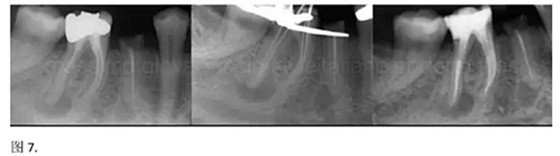

開髓后預(yù)敞、探查根管、建立直線通路是根管機(jī)械預(yù)備的第一步。在這些階段中,醫(yī)生可能會(huì)經(jīng)常遇到一些困難。這些難題包括器械折斷、臺(tái)階形成、根管歧坡或根管拉直、帶狀穿孔、根尖穿孔、根尖肘形、根尖堵塞。所有這些錯(cuò)誤可導(dǎo)致根管系統(tǒng)清潔不完善從而降低牙髓治療成功率。